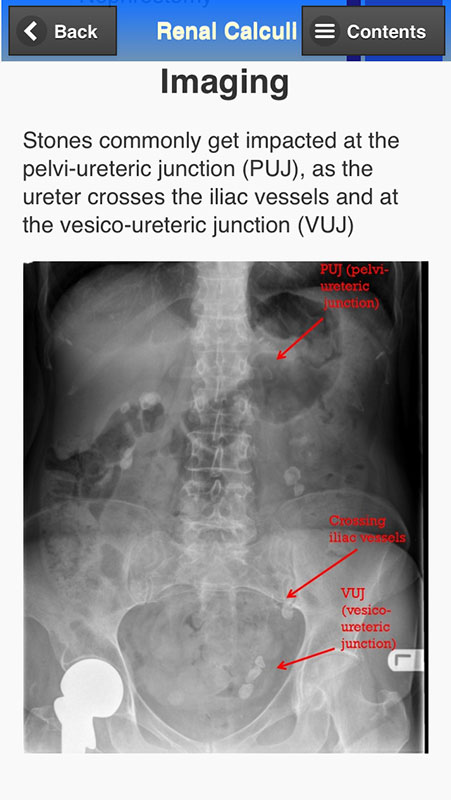

The app also contains photos depicting some of the conditions, their presentations, equipment, radiology scans, and so on.